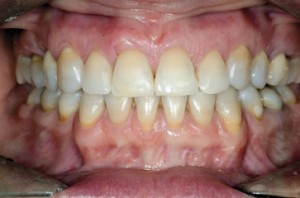

| Status tkanek miękkich po zakończeniu interdyscyplinarnego leczenia ortodontyczno-periodontologicznego | ||